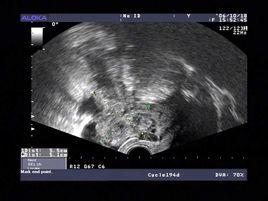

後穹窿穿刺術是穿刺後穹窿抽出液體用於檢查的手術。

陰道後穹隆穿刺術是婦科臨床常用的一種操作簡便而重要的診斷手術之一。主要用於了解子宮直腸窩有無積液及其性質;或用於貼近子宮直腸窩腫塊內容的性狀,藉以探究病...